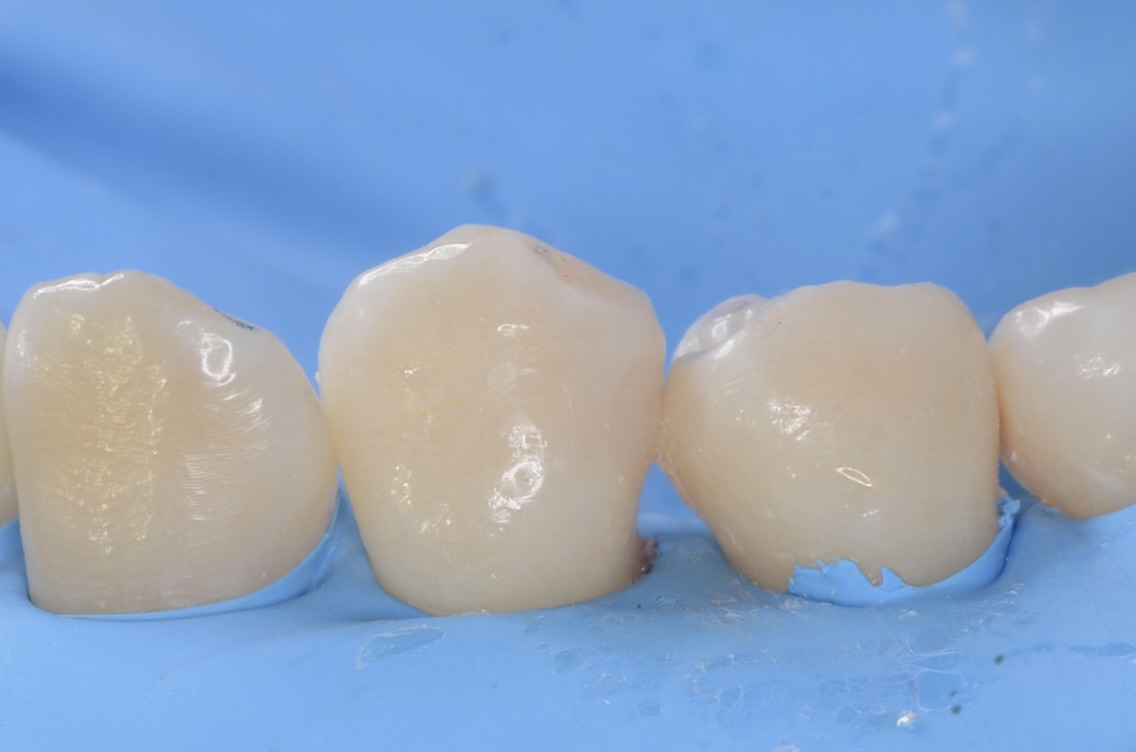

レジン充填完了

フロスを通してみて適切な、きつさがあるのを確認しています。 -

頬側面から見る

-

咬合面から見る

舌側面から見る

このように歯並びが若干乱れている場合の、歯と歯の間にできた虫歯治療は意外と難易度が高いです。しかしセパレーターを使って歯間離開させ、フロワブルレジンの表面張力を利用して充填すれば、滑らかで、引っ掛かりのない歯の形態を再現できます。